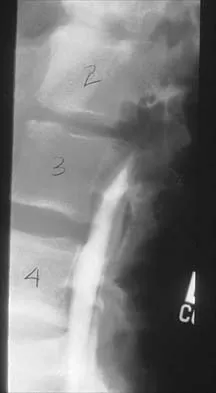

In patients with neurofibromatosis, what is the most important sign of impending rapid progression of a spinal deformity?

Explanation

Neurofibromatosis can progress very rapidly. Rib penciling is the only singular prognostic factor. Significant progression has been observed in 87% of the curves with three or more penciled ribs. The other factors are often present but do not have a high correlation with rapid, severe progression. Crawford AH, Schorry EK: Neurofibromatosis in children: The role of the orthopaedist. J Am Acad Orthop Surg 1999;7:217-230.